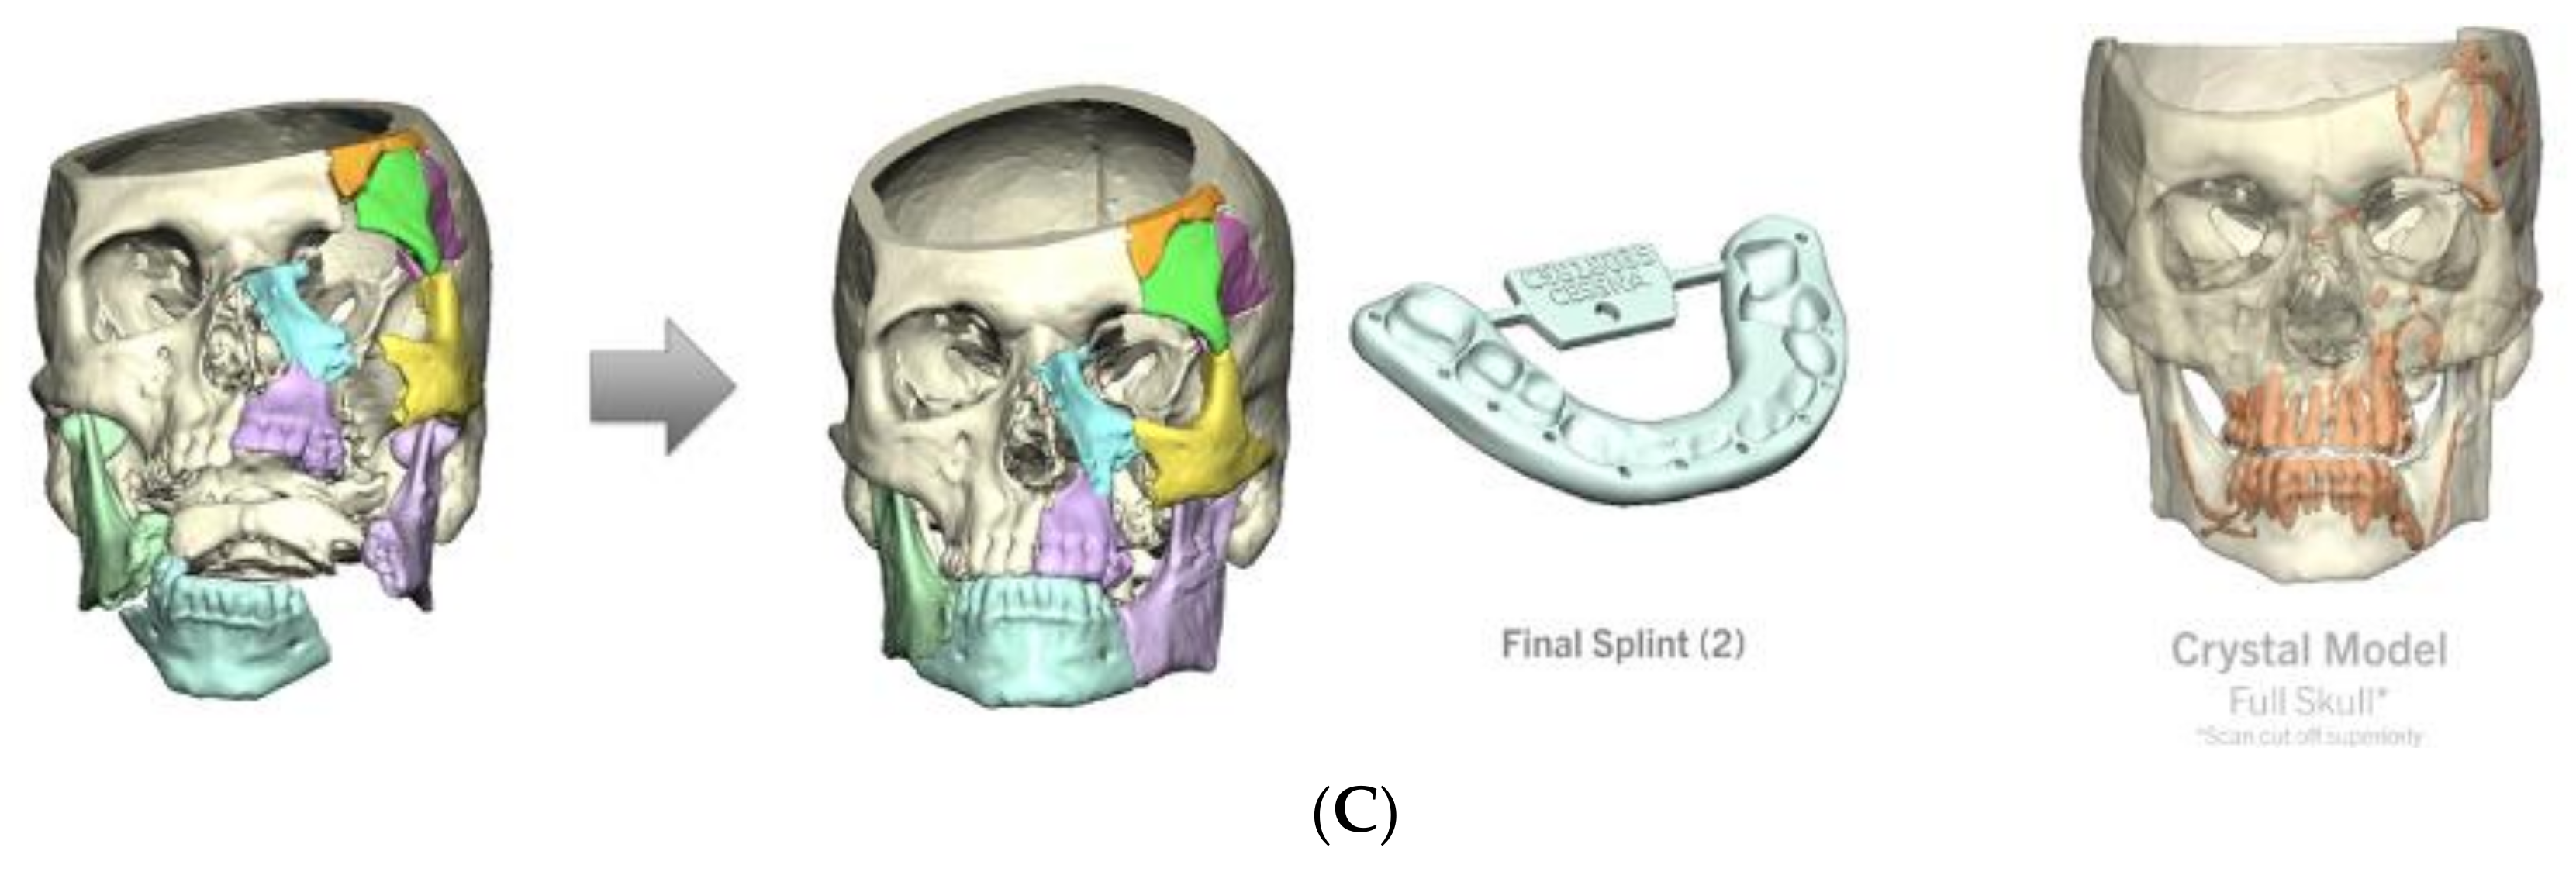

4.3. Case 3 (Patient 3D Model, Occlusal Splint, 3D Printed Plate)

- Left orbital floor and lateral orbital rim fractures;

- Comminuted maxillary fractures with involvement of the hard palate and retained bullet fragments in the maxillary sinus;

- An extensively comminuted open fracture of the left mandibular body extending to the parasymphysis;

- Extensive soft tissue and dental injuries with retained ballistic fragments.